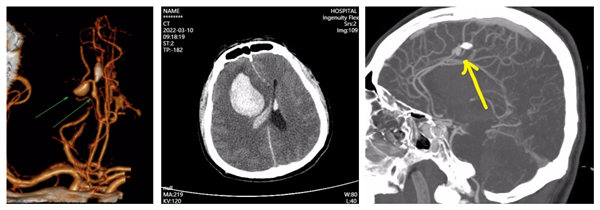

术前颅脑CT及CTA提示脑血肿及动脉瘤情况